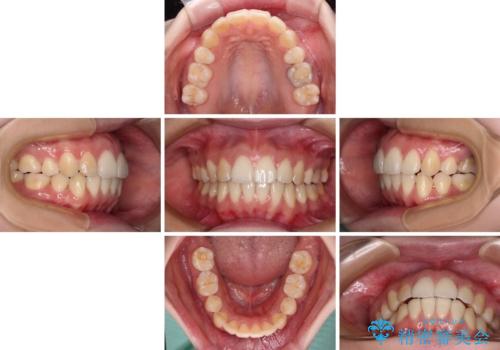

舌の突出癖が原因で後戻りをしたため、舌のトレーニングをしっかりと行っていただき、口元の突出感を改善することができました。

インビザラインの装着時間が守れず、1年強で終わる予定でしたが、4年間を要することとなりました。

- 矯正治療後の保定が不十分だと後戻り(元の位置に戻ろうとする動き)をします